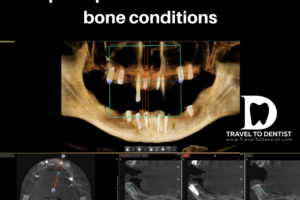

Can i place implants if i don’t have enough bone?

Definitely YES! Even if it does not have sufficient bone, there is still the possibility of inserting dental implants, using various methods, depending on the clinical case. These methods are:

- bone grafting through sinus lift, crestal expansion or other bone tissue regeneration procedures. Read more about: Bone grafting. Bone surgery prior to implantation;

- the all on 4 technique, when the implants are placed in the frontal area where usually the bone is kept longer;

- pterygoid implants, which are placed in the area of the wisdom tooth;

- zygomatic implants, which are inserted into the cheekbones (the zygomatic bone, also called malar bone). They are frequently used in case of severe bone atrophy over the entire dental arch.

The number of phases of a treatment with dental implants depends primarily on the situation of the bone. With new digital techniques and other methods of avoiding large bone grafts (which previously required supplementary visits), treatment can now be completed in 2 visits in most cases. To tell you for sure, it is advisable to send a 3D tomography, on the basis of which our dentist will immediately answer this question.

- the quantity and quality of the available bone in which the dental implants will be placed.